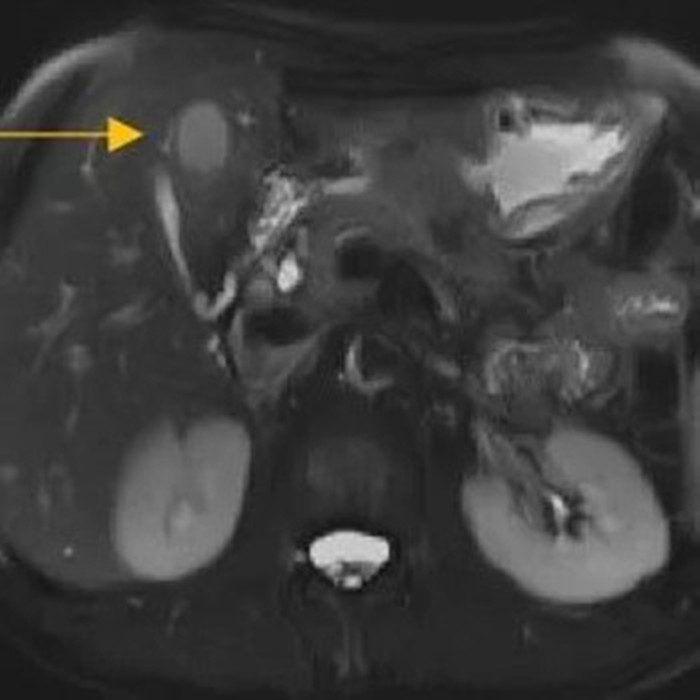

經(jīng)過6個周期,前后4個月的治療,周先生再次復(fù)查CT,提示胃部腫瘤,轉(zhuǎn)移的胃旁淋巴結(jié)、肝臟腫瘤都有明顯縮小,營養(yǎng)狀況良好,能正常進(jìn)食,體重增加了6斤,精神狀態(tài)比原先好了很多。

治療前

治療后

根據(jù)復(fù)查的CT結(jié)果,金尹和胃外科主任醫(yī)師余春,聯(lián)系了溫州醫(yī)科大學(xué)附屬第一醫(yī)院胃腸外科主任陳笑雷、閆競一團(tuán)隊,對周先生的病情再次進(jìn)行評估討論,認(rèn)為通過前期的轉(zhuǎn)化治療,效果顯著,建議手術(shù)根治。